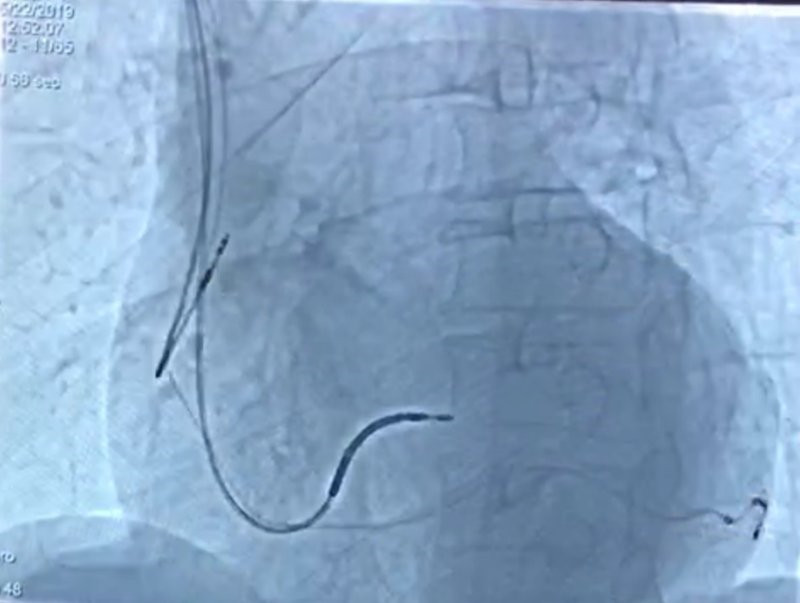

这位62岁男性患者入院诊断为扩张型心肌病,心功能不全NYHAIV级,心电图示完全性左束支传导阻滞QRS波群宽160ms,心脏超声显示左室舒张末期内径为6.8cm,而左室射血分数仅为26%,合并频发室性早搏、RonT、短阵室速,适合植入CRT-D。心血管内科一病区电生理团队综合患者适应症及预后多方面考虑,为其选择目前行业领先的具有左室多部位起搏功能的CRT-D,经前期充分准备,独立且顺利为患者植入MPP CRT-D。

手术过程顺利,患者自我感觉良好,术后心电图显示,QRS波群宽度为120ms,心脏激动延迟明显减少,左右室同步化增强,预示患者会有良好的恢复。可预见,随着CRT-D治疗时间的延长,同步化治疗效果进一步加强,患者心功能会进一步改善。